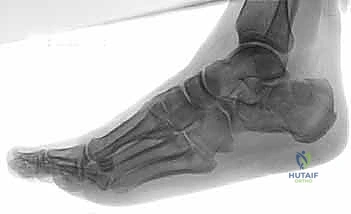

- التصوير بالأشعة السينية (X-rays): لأخذ فكرة أولية عن الكسر (زوايا بوهلر وجيسان - Bohler’s and Gissane’s angles).

- الأشعة المقطعية (CT Scan): وهي الخطوة الأهم والأكثر حيوية. توفر الأشعة المقطعية صوراً ثلاثية الأبعاد وتقاطعاً دقيقاً للكسر، مما يسمح بتصنيف الكسر (نظام ساندرز - Sanders Classification) وتحديد عدد الشظايا العظمية ومدى انزياحها داخل المفصل. بناءً على هذه الأشعة، يضع الدكتور هطيف خطته الجراحية الدقيقة.